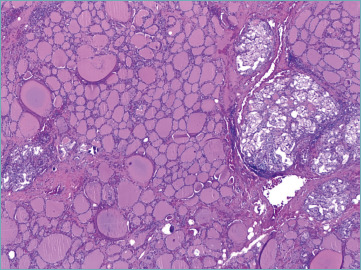

目的:美国甲状腺协会(ATA)更新了甲状腺癌治疗指南,根据临床病理特征采用了一种不那么激进的方法。因此,与全甲状腺切除术相比,行肺叶切除术的可能性显著增加。大多数甲状腺癌是惰性的,预后良好,而只有15%的高分化癌(包括乳头状甲状腺癌(PTC))患者在诊断时为局部晚期甲状腺癌(LATC)。我们回顾了过去十年来治疗甲状腺癌的实践。方法:对2010年1月至2020年12月1057例甲状腺单发良、恶性病变患者进行回顾性分析。结果:77%为女性,中位年龄49.3岁。307例恶性诊断(29.05%),其中经典PTC 196例(61.6%),侵袭性PTC 38例(12%),多为高细胞变异(30例,9.4%)。在恶性病例中,显微镜下发现84例(26.4%)为多灶性病变。采用ATA风险分布,低危239例,中危68例。第二次手术共对150例患者进行了评估,显示42例患者在另一侧肺叶有额外的甲状腺癌灶(26例单发灶vs 16例多发灶)。甲状腺周围淋巴结转移10例。结论:我们的数据可以作为进行纵向研究的基础,以确定哪些危险因素可以预测双侧受累,并建议量身定制的手术方法。

Results: Among these cases, 77% were women with a median age of 49.3 years. The series involved 307 malignant diagnoses (29.05%) including 196 (61.6%) classic PTC and 38 (12%) aggressive variants of PTC, mostly tall cell variant (30 cases, 9.4%). Among malignant cases, multifocality was microscopically documented in 84 cases (26.4%). Using the ATA distribution of risk, there were 239 cases in the low risk and 68 in the intermediate risk categories. Second surgery was assessed in a total of 150 cases, showing 42 cases with additional thyroid cancer foci in the other lobe (26 single vs 16 multiple foci). Ten cases had metastatic perithyroidal lymph nodes.